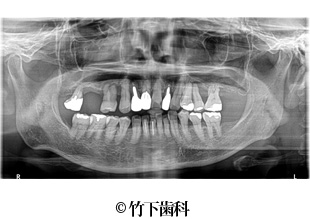

【症例1】上顎臼歯部のインプラントによる治療

- 治療前

- 治療後

- 治療名

- 上顎臼歯部のインプラントによる治療

- 費用

- 275,000円(税込)

【内訳】

インプラント埋入術

220,000円(税込)

インプラント上部構造

55,000円(税込)

- 期間

- 7ヵ月

- 通院回数

- 8回

- 患者様

- 30代女性

治療内容

-

患者様の症状

奥歯に痛みを感じて来院し、レントゲンで右側臼歯の歯根破折が確認されたため抜歯しました。欠損部分をインプラント治療することを希望されました。また、隣接歯をイプラントの色にそろえたいというご希望がありました。

治療法

歯根破折を起こした右側臼歯に代わって、顎の骨にインプラント(人口の歯の根)を埋め込む治療を行いました。その後、インプラントには人口の歯を被せることで機能面の回復をする治療を行っています。

同時に隣接した補綴物の金属色が気になるとのことでしたので、補綴物を公的医療保険適応のCAD/CAM冠に変更しました。 -

治療結果

インプラント治療によって歯根破折を起こした歯を補うことができ、審美面・機能面の回復に繋がりました。

※治療結果は患者様によって個人差があります。

治療を行う上での 注意点 (リスク・副作用)

出血、腫脹、疼痛、神経麻痺、補綴物のダツリ、破折、インプラント体の破折、咬合違和感、インプラント周囲炎